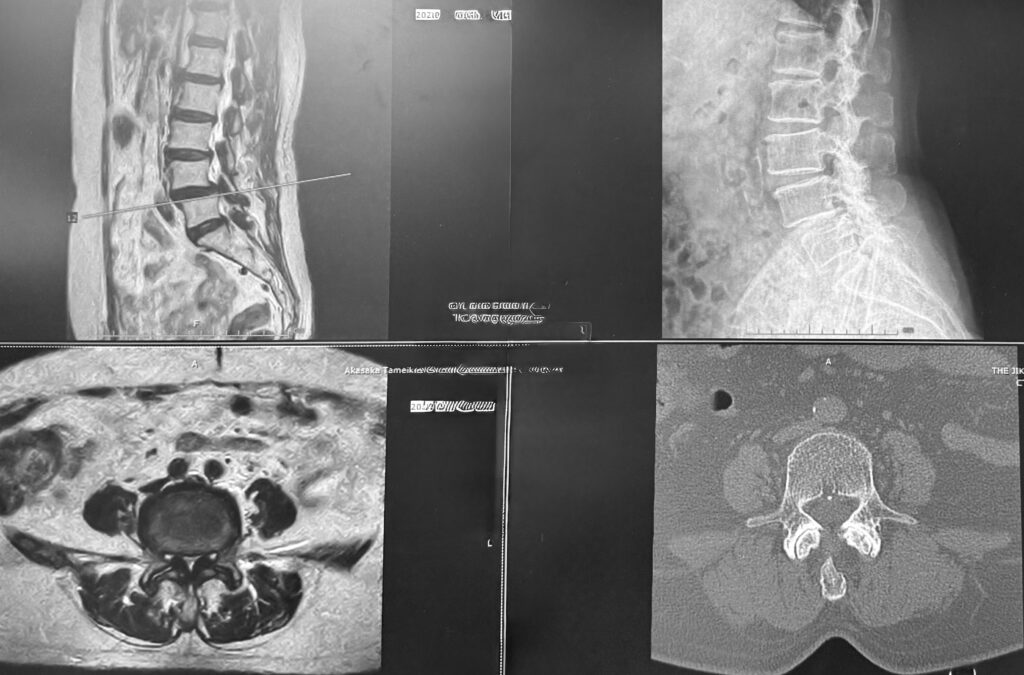

この患者さんの画像ですが、L4/5が滑って狭窄症をきたしています。